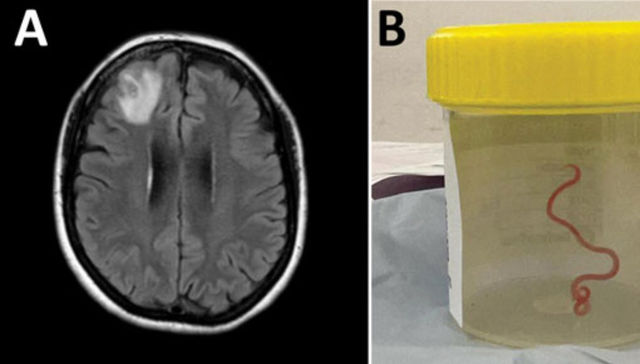

Caso único en el mundo: hallan un parasito intestinal de 8 cm en el cerebro de una mujer